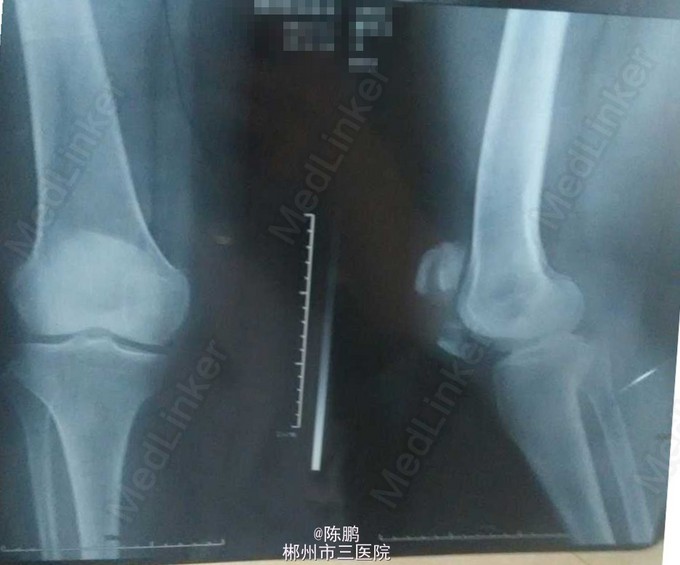

患者老年女性,60岁; 主诉:外伤右膝部肿痛,不能活动1小时。 现病史:患者1小时前不慎摔伤,右膝部着地,即感右膝部疼痛,不能活动,为求明确诊断遂来我院。

专科体查:右膝部中度肿胀,局部皮肤青紫,无皮肤破损,压痛,可扪及明显骨擦感及闻及骨擦音。右膝关节活动受限,浮髌试验(+),肢端感觉,血运好,足趾活动好,左下肢,双上肢,脊柱活动好,无畸形。 辅助检查:右膝关节正侧位:右髌骨骨折

初步诊断:右髌骨骨折 在腰麻下行右髌骨骨折开放复位髌骨爪内固定术